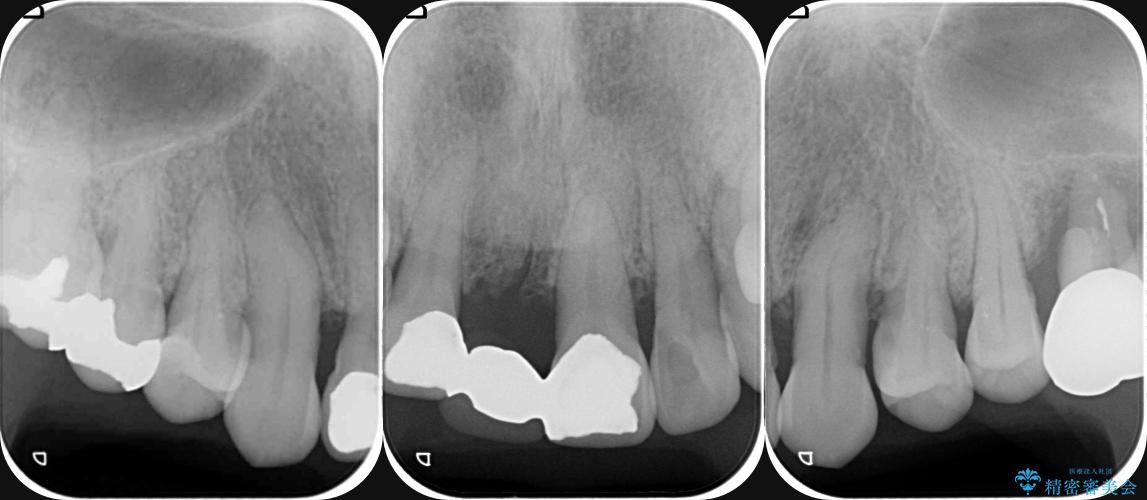

検査の結果、歯周ポケットの測定値は4-6mm程度の値が全顎にわたって認められ、中等度歯周病の状態です。

歯を今後残し、歯周病の状態を改善するため、歯槽骨の再生治療をおこなったのち、歯周ポケットの除去、セラミックブリッジの製作を行う治療計画を実行していきます。

歯周病によって失われた歯を支える骨(歯槽骨)に対し、再生療法を用いることで骨の再生・回復を実現しました。骨の高さが改善されたことで、歯の土台が強化され、将来にわたって歯をしっかりと支え続けられる口腔内環境を整えることができました。